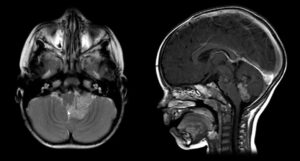

Enfermedades Cerebrovasculares

Las Enfermedades Cerebrovasculares son una de las causas más frecuentes de morbimortalidad según la OMS (Organización Mundial de la Salud). Estas enfermedades comprenden a un diverso grupo de patologías que causan alteraciones en el flujo sanguíneo cerebral pudiendo causar afecciones devastadoras.

Aneurisma Cerebral

Un aneurisma es la dilatación de un vaso sanguíneo en el cerebro, generalmente una arteria cerebral. Estos aneurismas están formados por una debilidad de la pared de la arteria formando una dilatación que, debido a la debilidad de su pared, tiene riesgo de romperse.